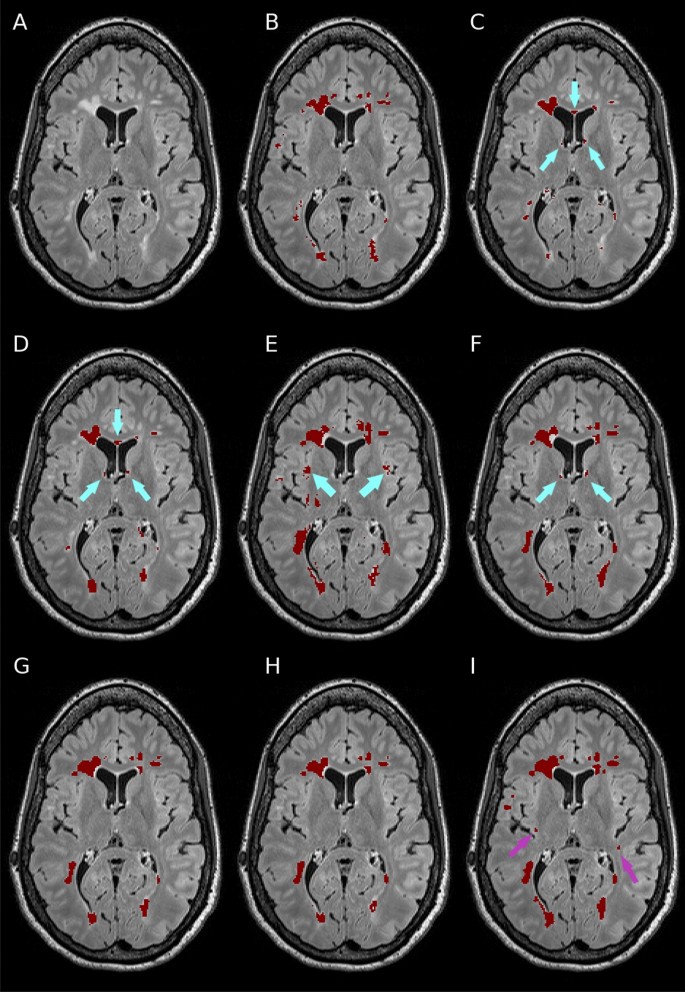

Performance metrics on the Insel32 dataset (vs the consensus segmentation) are summarised in Table 2, along with inter-rater comparison between the two raters, and between the raters and the consensus. An example of output of the methods considered, together with the manual ground truth, can be seen in Fig. 2.

Example segmentations of a case from the Insel32 dataset, axial view. (A) FLAIR image, plus segmentations from (B) manual raters, (C) LPA, (D) LGA, (E) nicMSlesions and (F) nnUnet (all labels) (G) DeepSCAN (just lesions) (H) nnUnet (just lesions) (I) DeepSCAN (all labels). Segmentations from LGA, LPA, and nnUnet (all labels) show erroneous segmentation of healthy-appearing tissue near the ventricles (cyan arrows). nicMSlesions labels healthy cortical grey matter as lesion tissue (cyan arrows) DeepSCAN (all labels) identified two subtle lesions (violet arrows) missed by the manual raters but subsequently confirmed by our experienced neuroradiologists.

We performed Wilcoxon signed-rank tests of the differences between the methods, with a significance level of 0.05. All DeepSCAN and nnUnet models trained performed significantly better than LPA, LGA and nicMSlesions, according to both Dice coefficient and F1 score. No significant difference was found between the Dice coefficients of DeepSCAN (lesions only), DeepSCAN (lesions and brain structures) and nnUnet (lesions only): these three methods were significantly better regarding Dice coefficient than nnUnet (lesions and brain structures). Regarding lesion detection (lesion F1 score), DeepSCAN (lesions and brain structures) was significantly better than all other methods.